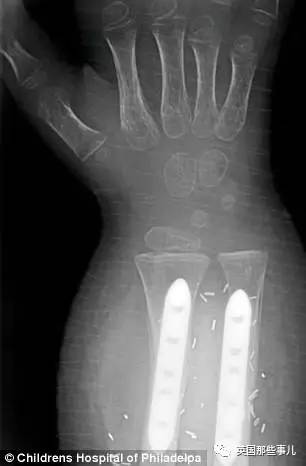

Zion在费城儿童医院进行了一项非常前沿,风险也很大的手术:

双手移植。

在之前,这项手术虽然已有先例,

但要么是单手移植,要么是成年人,要么,是同卵双胞胎之间进行移植,

就算这样,还出现过移植者术后不久就因为并发症去世的情况。

一个几岁的小孩子,双手移植……

这在美国,还是第一次。

手术进行了整整11个小时,

40名医生、护士聚集在手术室里,

一切,都紧张却又有条不紊地进行着……

最后,几乎累到虚脱的医务人员把Zion推出手术室,

“手术成功了。”

他新的双手来自一名意外死亡的捐赠者,

这双陌生的手,能不能与他的身体和谐相处还是个问题。